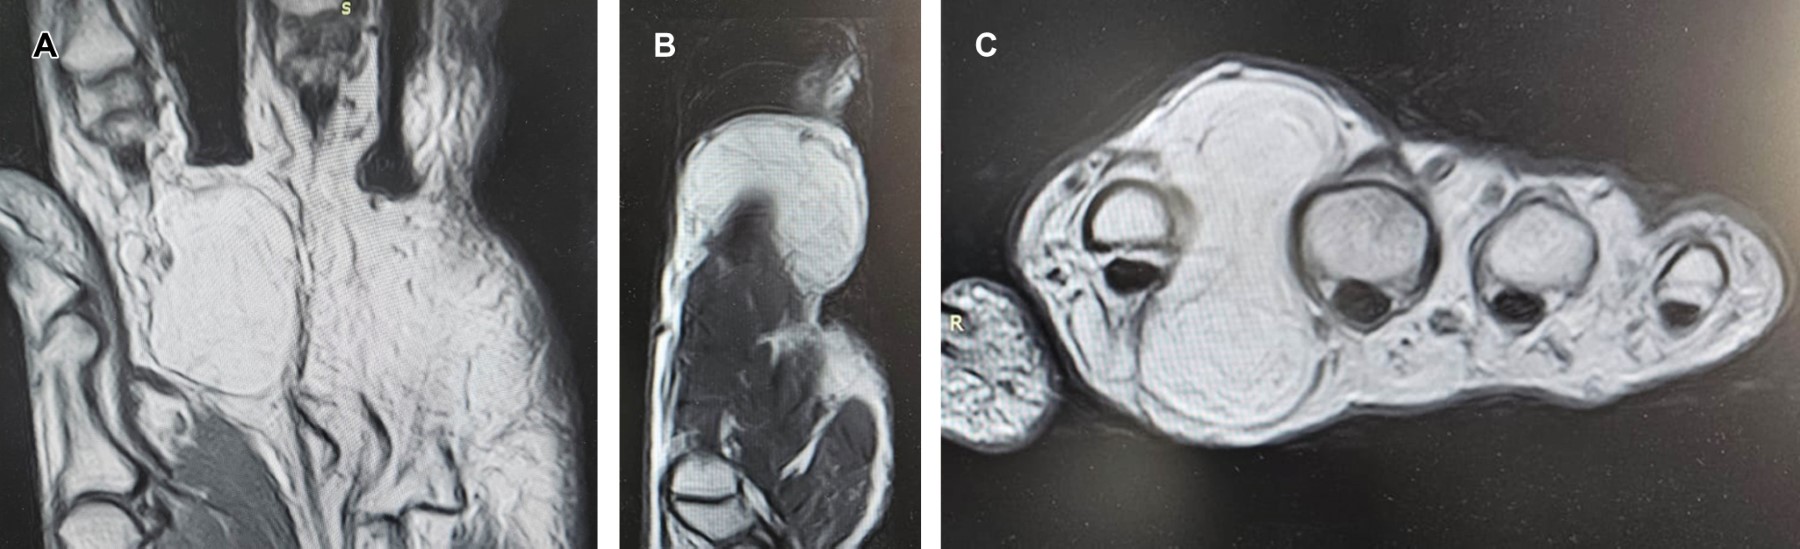

Lipofibroma of the hand is infrequent, with a mean age of presentation of 55 years. Their typical location is the thenar, hypothenar, and commissure eminences. They are usually larger than the rest of the primary soft tissue tumors when they occur in the commissure and are transferred to the dorsal compartment. They are usually not painful. The study of choice for diagnosis is magnetic resonance imaging, which shows a homogeneous image of increased intensity in T1 weighting. The types found in the hand are classic lipoma, angiolipoma, and tendon sheaths.

Figure 2